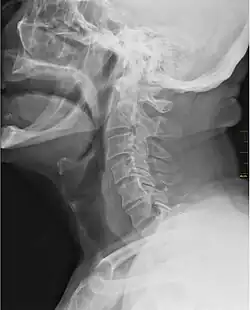

![]() X-ray showing the throat, seen as a dark band to the front of the spine | |

In vertebrate anatomy, the throat is the front part of the neck, internally positioned in front of the vertebrae. It contains the pharynx and larynx. An important section of it is the epiglottis, separating the esophagus from the trachea (windpipe), preventing food and drinks being inhaled into the lungs. The throat contains various blood vessels, pharyngeal muscles, the nasopharyngeal tonsil, the tonsils, the palatine uvula, the trachea, the esophagus, and the vocal cords.[1][2] Mammal throats consist of two bones, the hyoid bone and the clavicle. The "throat" is sometimes thought to be synonymous for the fauces.[3]

It works with the mouth, ears and nose, as well as a number of other parts of the body. Its pharynx is connected to the mouth, allowing speech to occur, and food and liquid to pass down the throat. It is joined to the nose by the nasopharynx at the top of the throat, and to the ear by its Eustachian tube.[4] The throat's trachea carries inhaled air to the bronchi of the lungs. The esophagus carries food through the throat to the stomach.[5] Adenoids and tonsils help prevent infection and are composed of lymph tissue. The larynx contains vocal cords, the epiglottis (preventing food/liquid inhalation), and an area known as the subglottic larynx, in children it is the narrowest section of the upper part of the throat.[6][7]